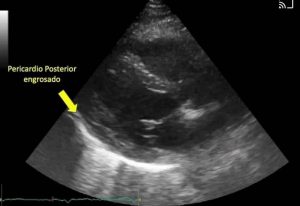

CASO CLINICO DE PERICARDITIS

Ver Más »